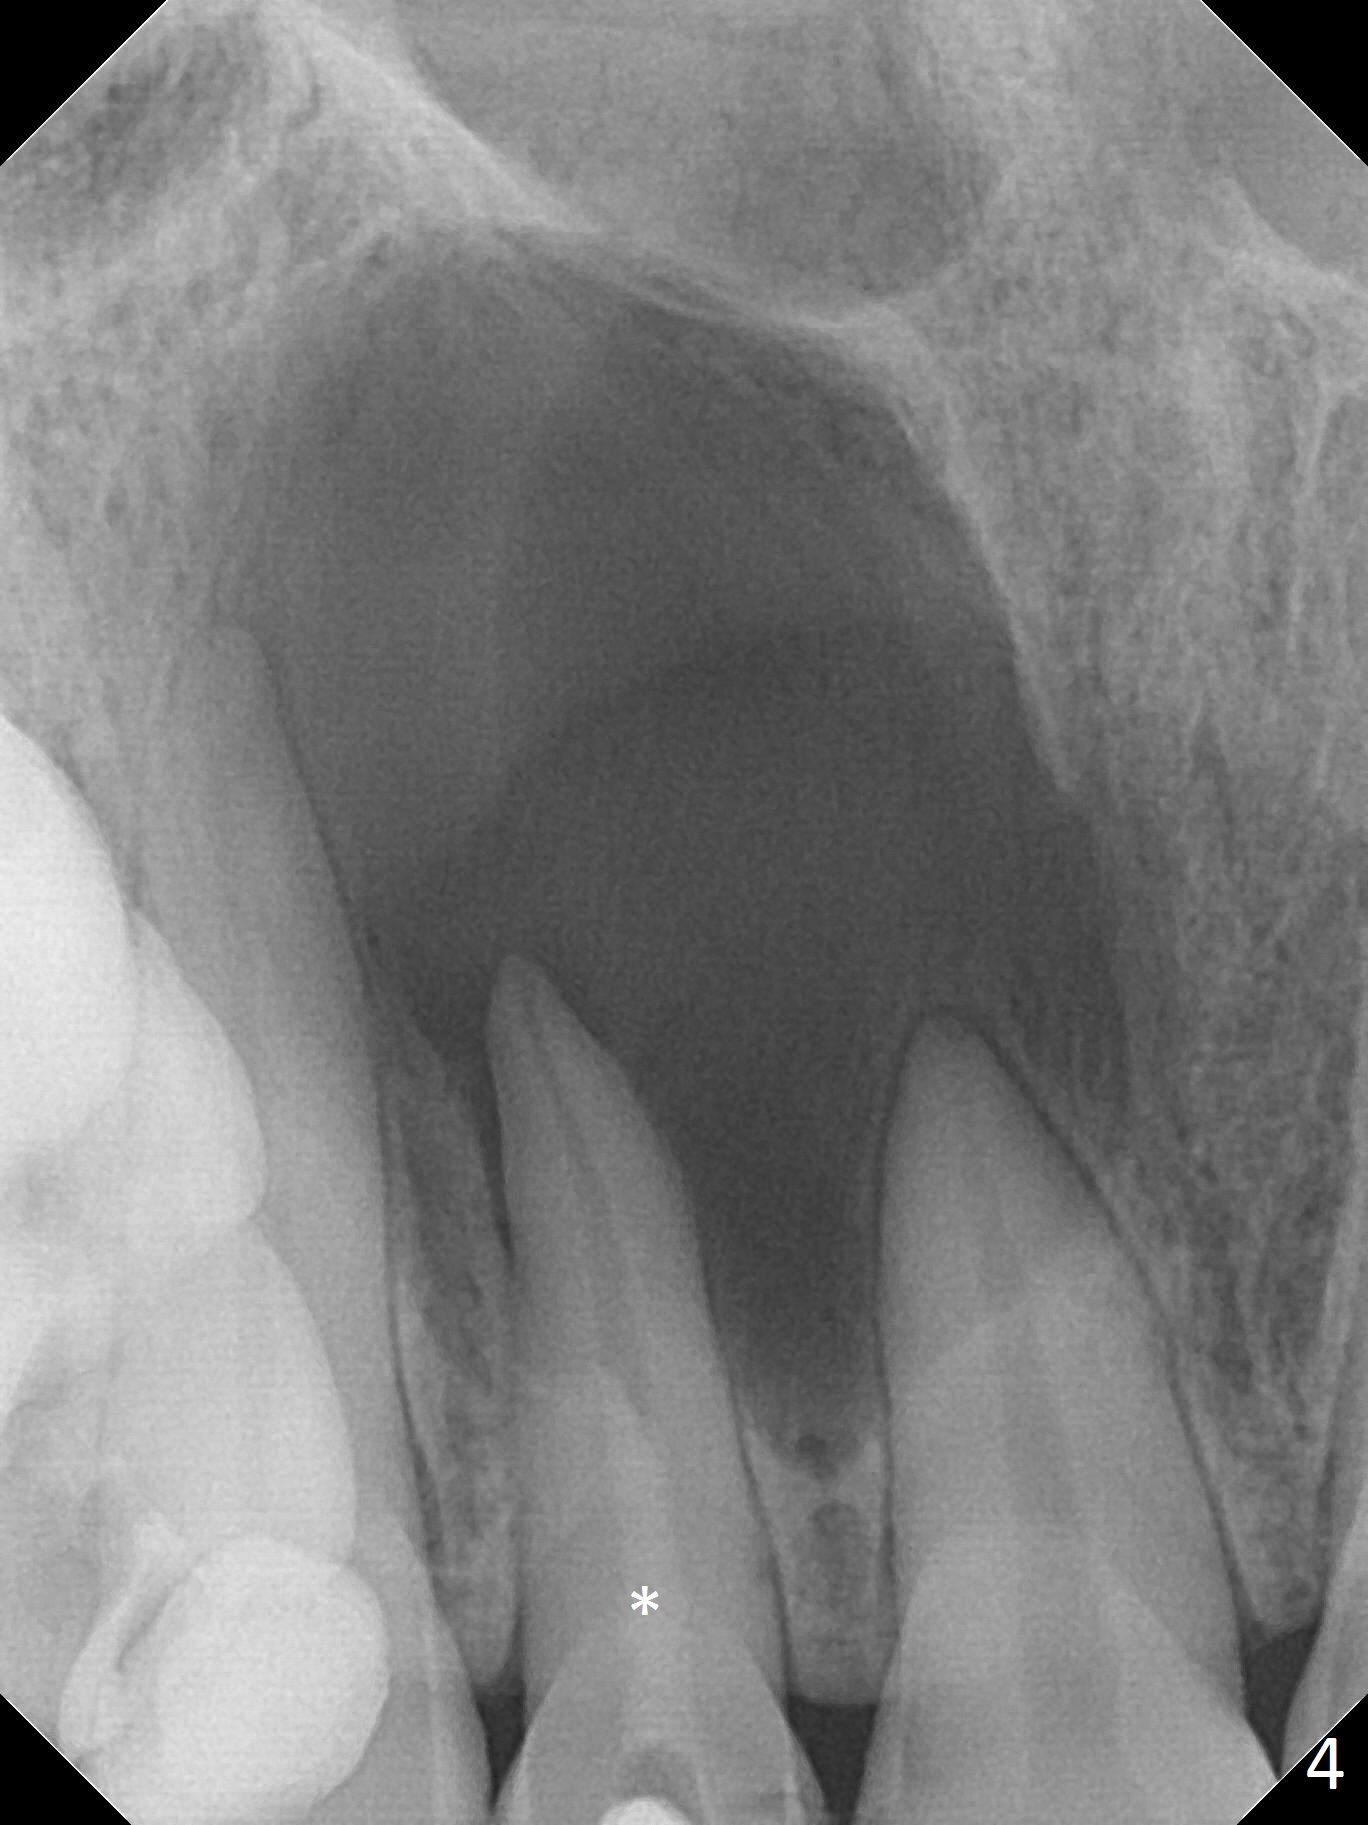

A 30-year-old woman presents to clinic with a large palatal swelling (Fig.1,2). In fact the tooth #7 is necrotic with a periapical radiolucency (Fig.2 arrowheads). RCT is initiated; note the curved canal and file (Fig.3). To reduce the large lesion, Calcium Hydroxide paste is placed in the enlarged canal (Fig.4 *). In a month, the palatal lesion decreases (Fig.5). After re-debridement of the canal, Calcium Hydroxide paste is re-applied.